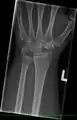

Left hand x-ray with Kienbock's Disease showing 4 mm negative ulnar variance and Kienbock's Disease Stage IIIB

X-ray showing stage IIIB on right wrist, with ulnar impingement.